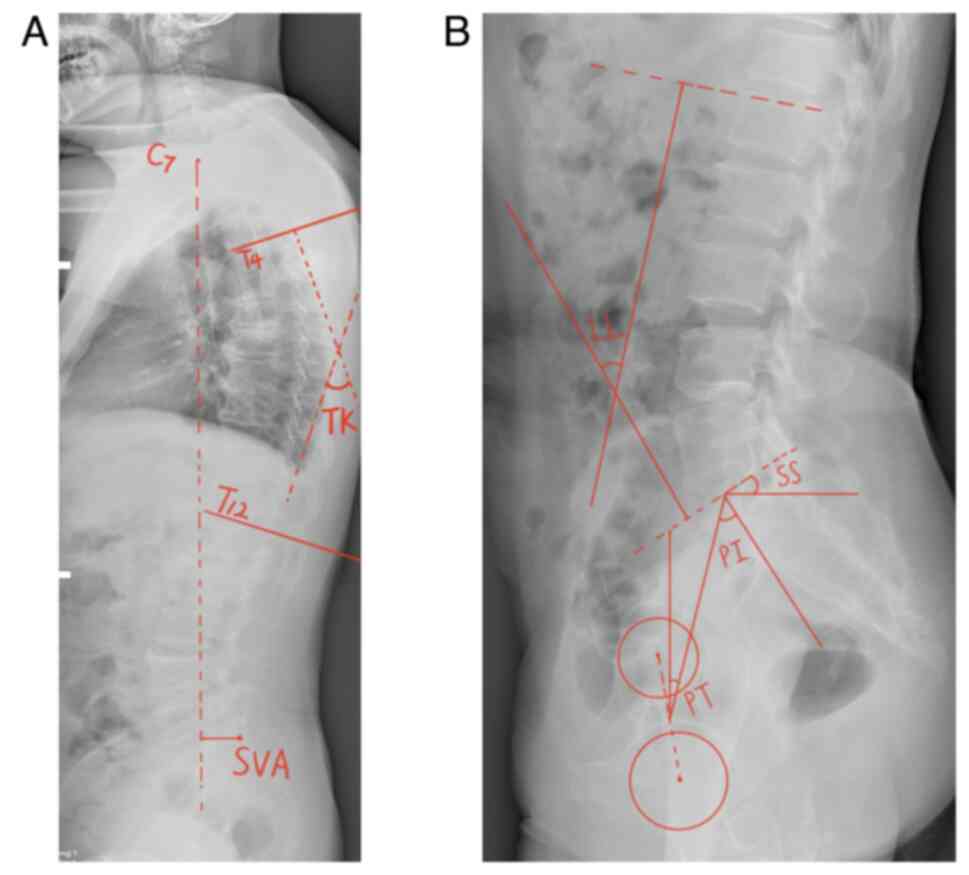

Surgimap allowed the measurement of spine-related parameters. Lafage et al (14) confirmed that the application of Surgimap to calculate the relevant parameters had the advantages of shorter processing periods, less errors and easier data storage compared with traditional manual methods, and was thus suitable for clinical use. Full-length X-ray lateral images of the standard spine as JPG files were imported from the Radiology Department into Surgimap to measure the spinal sagittal parameters separately according to the corresponding operating criteria (Figs. 1 and 2).

Figure 1

Measurement diagram developed using Surgimap. (A) LL, the angle formed by the tangent of the upper edge of the L1 vertebral body and the tangent of the upper endplate of the S1 vertebral body. (B) TK, the angle formed by the tangent of the upper edge of the T4 vertebral body and the tangent of the lower edge of the T12 vertebral body. (C) PT, passing through the middle of the upper endplate of S1, a straight line between the point and the midpoint of the line connecting the centers of the bilateral femoral heads was added in order to exhibit the angle formed by the straight line and the long axis of the body. SS, the angle formed by the tangent line of the upper endplate of S1 and the horizontal line. PI, a straight line through the midpoint of the line connecting the midpoint of the upper endplate of S1 and the center of the bilateral femoral heads was added. The angle formed by the vertical line of the upper endplate of S1 is depicted. (D) SVA, the distance between the plumb line of the seventh cervical vertebra and the posterior upper angle of the first sacrum. LL, lumbar lordosis; TK, thoracic kyphosis; PT, pelvic tilt; SS, sacral slope; PI, pelvic incidence; SVA, sagittal vertical axis.

Figure 2

Spine-pelvic parameters measured using Surgimap. (A) TK, the angle formed by the tangent of the upper edge of the T4 vertebral body and the tangent of the lower edge of the T12 vertebral body. SVA, the distance between the plumb line of the seventh cervical vertebra and the posterior upper angle of the first sacrum. (B) LL, the angle formed by the tangent of the upper edge of the L1 vertebral body and the tangent of the upper endplate of the S1 vertebral body. PT, passing through the middle of the upper endplate of S1, a straight line between the point and the midpoint of the line connecting the centers of the bilateral femoral heads was created, and the angle formed by the straight line and the long axis of the body is depicted. SS, the angle formed by the tangent line of the upper endplate of S1 and the horizontal line. PI, a straight line through the midpoint of the line connecting the midpoint of the upper endplate of S1 and the center of the bilateral femoral heads was added. The angle formed by the vertical line of the upper endplate of S1 is revealed. LL, lumbar lordosis; TK, thoracic kyphosis; PT, pelvic tilt; SS, sacral slope; PI, pelvic incidence; SVA, sagittal vertical axis.